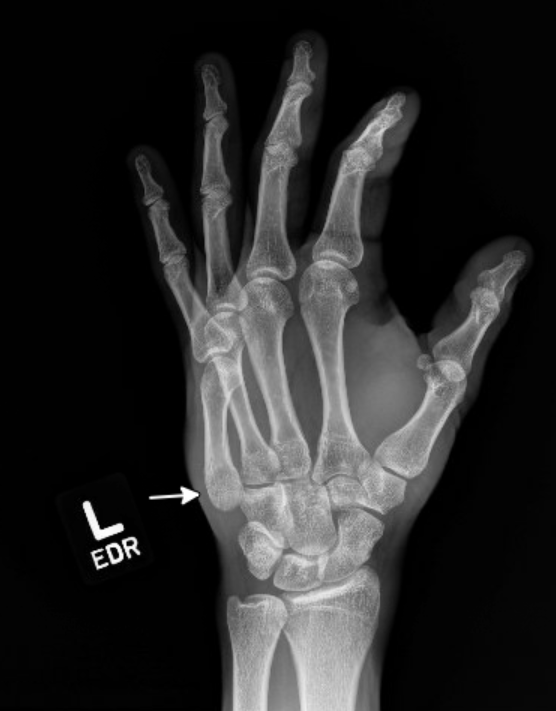

The patient punched a wall in an episode of frustration with his left hand and has pain and swelling over the ulnar aspect of his hand and wrist. What is the diagnosis?